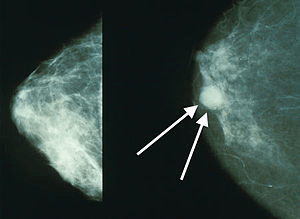

Най-общо можем да разделим рака на гърдата на ранен и напреднал. Ясното разграничаване обаче на тези две състояния понякога също е трудно. Към ранния карцином на гърдата със сигурност спадат туморите без далечни метастази, с размер на тумора до 5 см, без ангажиране на кожата или гръдната стена и без метастази в лимфните възли.

За да се установи, от кой молекулен тип е рака на гърдата и има ли експресия на рецепторите е необходимо провеждането на дебелоиглена биопсия, за която процедура може да прочетете повече ТУК. Както става ясно има много фактори, които трябва да са известни, за да може да се планира кога и дали да се извърши операция. Задължително е извършването на дебелоиглена биопсия и опеределяне на рецепторния статус, задължително е наличието на образни изследвания, които да покажат има ли ангажирани лимфни възли подмишницата. Веднъж имайки тези изледвания, е възможно да се наложи извършването на още по подробни образни изследвания- ядрено-магнитен резонанс, скенер с контраст или PET скенер и чак тогава може да се помисли за това кога и какво да се оперира.